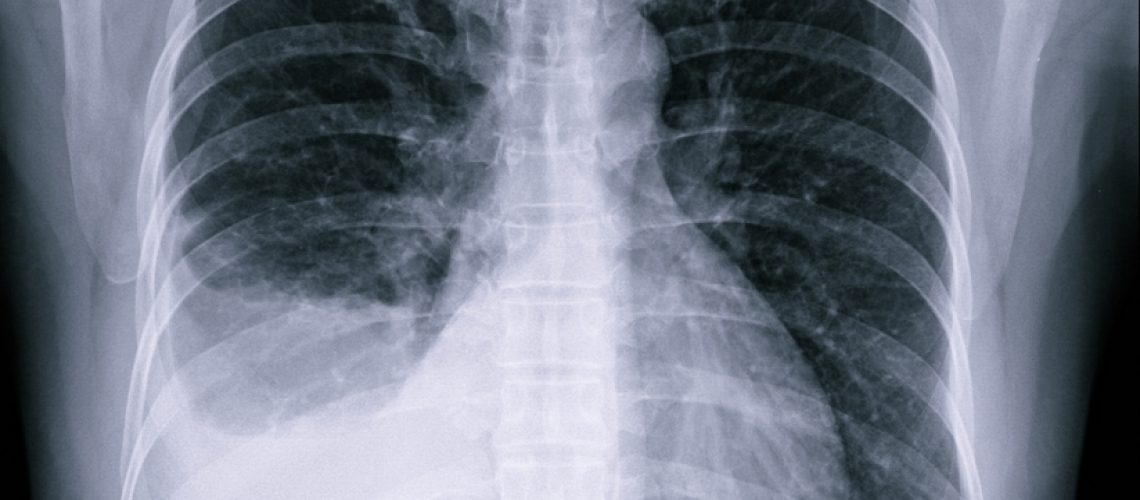

Na ocorrência de múltiplos sintomas, é imperative procurar assistência médica imediatamente para um diagnóstico apropriado através de exames como raio-X do tórax e análises laboratoriais.

O diagnóstico de edema pulmonar envolve uma avaliação abrangente dos sinais clínicos e histórico médico do paciente. O exame físico é crucial, com o médico realizando auscultação para detectar anomalias respiratórias. Além disso, os exames de imagem, como raios-X e possíveis tomografias, são essenciais para visualizar a extensão do líquido nos pulmões. Testes adicionais, como eletrocardiograma e ecocardiografia, podem ser necessários para investigar causas cardíacas subjacentes. Nos casos de infecção ou problemas cardiovasculares, exames de sangue também são fundamentais para determinar o nível de gases no sangue e a função cardíaca.